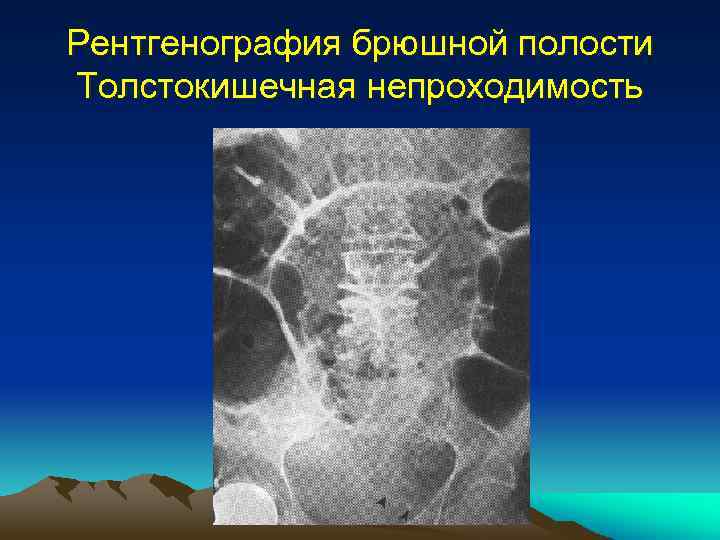

Нормы обзорной рентгенографии брюшной полости